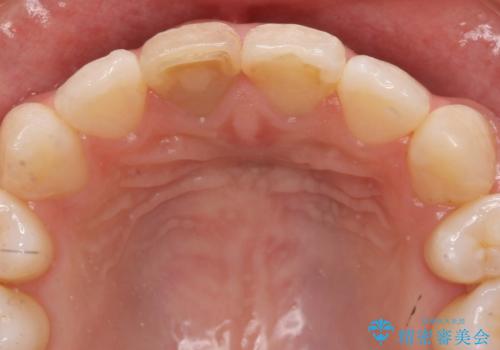

- 神経のない前歯が変色していたため、矯正治療後にセラミックで修復しました。

セラミックの前に、全体をオフィスホワイトニング(エクセレント)して周りの歯を白くして色をなじませました。

右の前歯は当院で根管治療をやり直しています。(根管治療はDr.大元が担当しました。)

神経をとった前歯は変色してきますので、セラミックで被せた方が良いです。

また、神経が無い歯は虫歯になっても自覚症状が出ないため、劣化するプラスチックで継ぎはぎするのは変色も防げないですし、オススメしません。歯が薄くなっており、破折のリスクがあるため、クラウンをおすすめします。